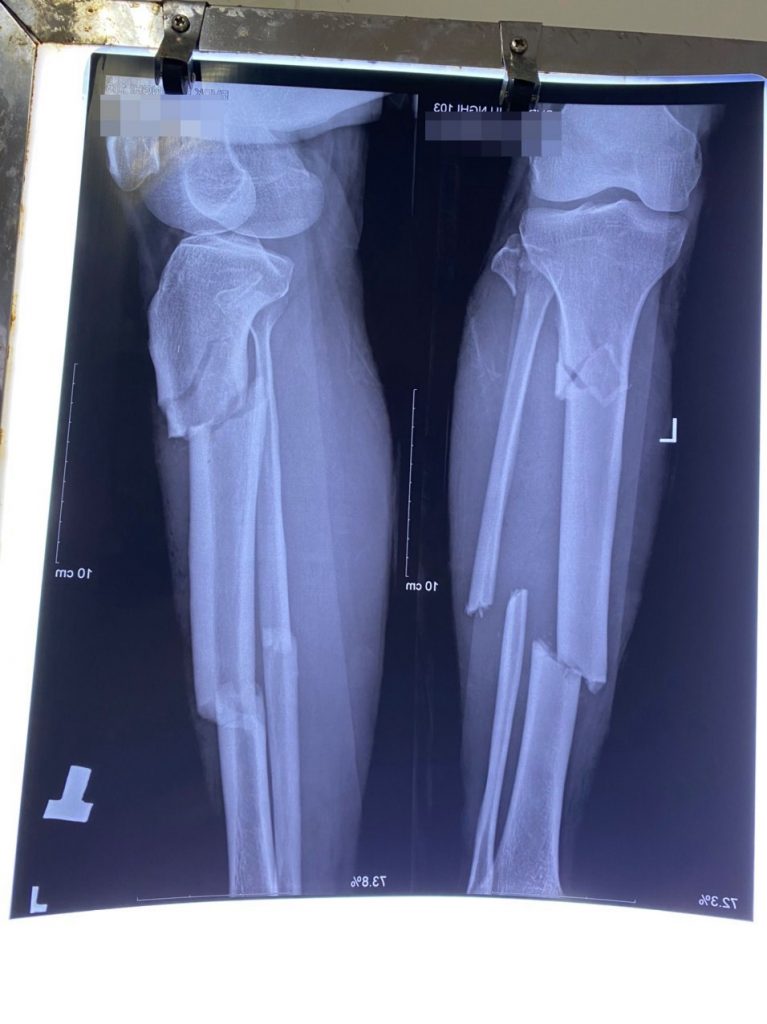

Ngày 24/09/2021, bệnh nhân Bàn Văn Đ. có địa chỉ ở xã Tân Hương, huyện Yên Bình, tỉnh Yên Bái khi đi khai thác gỗ do sơ ý bị cây to đè vào cẳng chân, được người nhà đưa vào bệnh viện đa khoa Hữu Nghị 103 trong tình trạng có vết thương chảy máu, đau chói, hạn chế vận động vùng cẳng chân trái, đã được gia đình xử trí tạm thời.

Sau khi được bác sĩ thăm khám, chụp X-Quang; kết quả chẩn đoán bệnh nhân bị gãy hở độ I, hai xương cẳng chân trái phức tạp do TNLĐ.